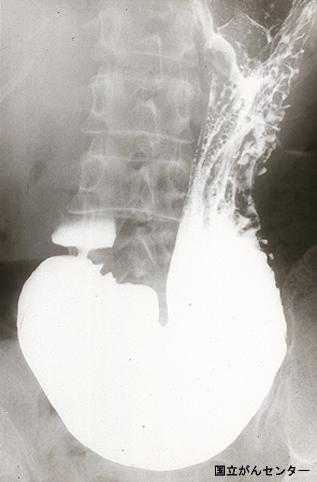

疾患(病理主体)の分類悪性上皮性腫瘍/腺癌

部位(臓器別)胃(部位)/体部

検査方法X-P

腫瘍の肉眼分類0型(表在型)/I型(I)

病変の最大径(ミリ)40以上

腫瘍の深達度sm